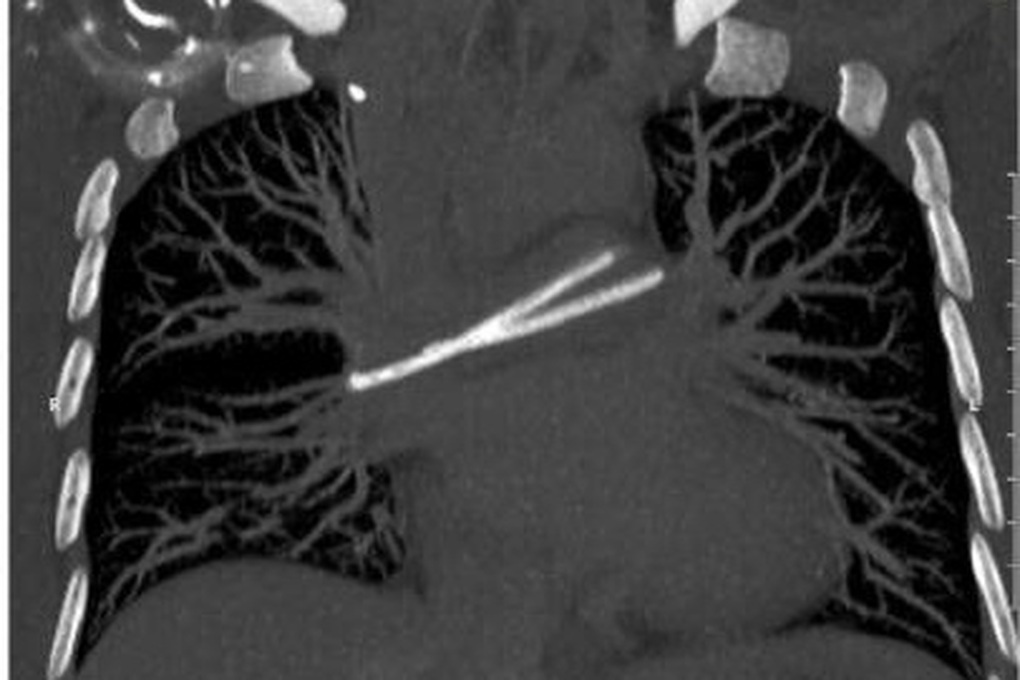

Trong một lần đi khám tầm soát, chị T. được chỉ định chụp CT ngực có tiêm thuốc cản quang và phát hiện hình ảnh một dị vật trong tim, nằm vắt ngang tại vị trí động mạch phổi hai bên, cần thực hiện thủ thuật can thiệp lấy ra.

Hình ảnh chụp chiếu ghi nhận dị vật trong tim, nằm vắt ngang động mạch phổi của bệnh nhân (Ảnh: BV).

Trở lại bệnh viện từng điều trị ung thư, bệnh nhân được chụp X-quang ngực và ghi nhận catheter đã bị đứt, phần đầu đã di chuyển về tim và nằm trong động mạch phổi.